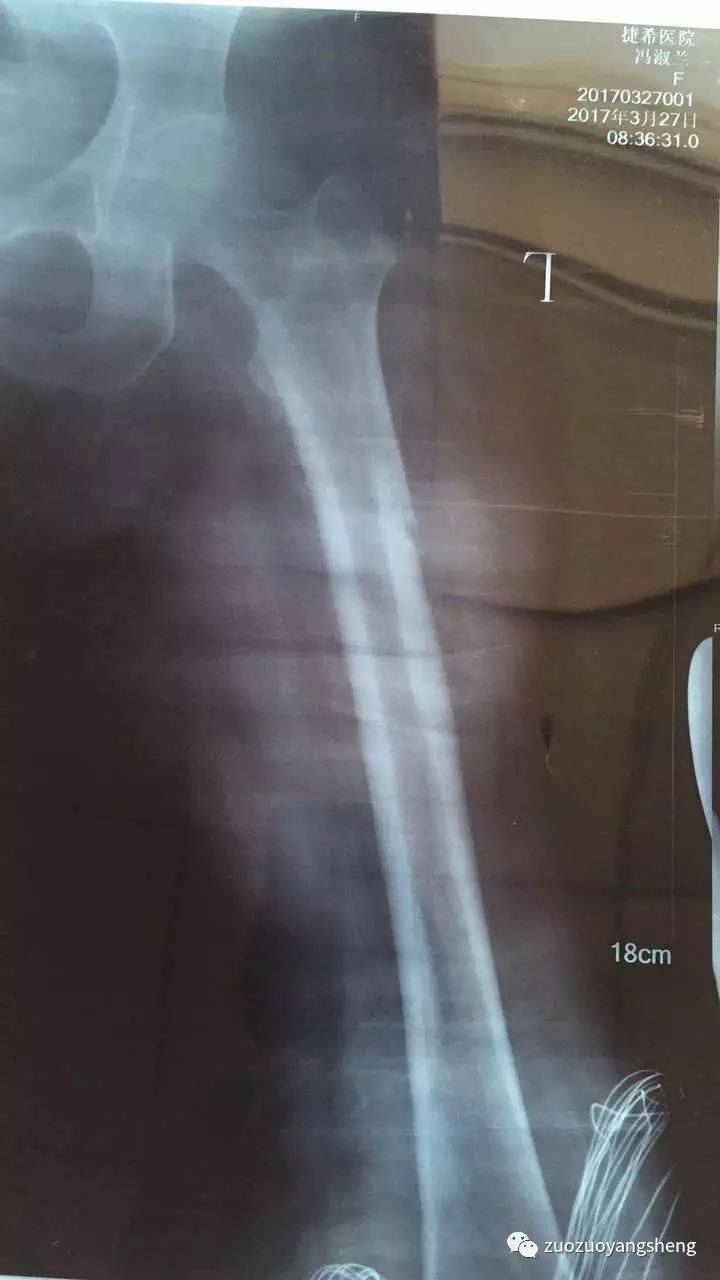

大家好,我是左左。在我收到方老师发过来的案例时,比较震惊,80几岁的婆婆能在短短几周里迅速愈合,确实有点不可思议。婆婆在某三甲医院的时候,医生是建议手术,而且必须手术。当家人选择保守治疗,选择使用原始点,才发现保守治疗的效果比手术治疗的效果更好,伤害更少,费用更低。

收到案例后的当天晚上,我就在想,自己母亲的粉碎性骨折是否也可以手法复位,保守治疗呢?然后开始陷入深深的自责中。去年母亲髌骨粉碎性骨折后,医院强烈建议手术治疗,说保守治疗可能需要在床上躺6个月,而且不能随意挪动。所以自己当时考虑到母亲不能动,长时间不能动,不能下床,更不能运动,这样下去怕影响整个身体,后决定采用医生建议,进行手术治疗。现一路走来,手术治疗这个方案,不到万不得已,原始点家人们尽量不要使用。手术前需要打针消炎(寒凉药物),手术中需要切割皮肤、肌肉等各身体组织,需要打麻药(超级寒凉药物),需要打钢钉固定骨头,手术后同样需要7天输液消炎(寒凉药物)……半年后还需要手术取出钢钉,还需要消炎(还好当时医院床位紧张,所以没有消炎,让回家自行打针消炎,我强烈反对,所以没打。)经过这样伤害性的治疗方法,虽然有给母亲使用原始点,按推、温敷和喝姜汤,但母亲的脚还是没能完全恢复。骨折至今已经8个月了,走路依然是一瘸一拐,膝关节里面还经常感觉紧绷,经常感觉疼痛。

如今,跟方老师提供的案例进行对比,骨折后选择手术治疗方案真的不是最佳治疗方案,遇到类似情况,特别是年轻人、小朋友,如果在遇到骨折后,选择保守治疗方案,配合使用原始点,因为身体热能足,也许修复起来更快更好。